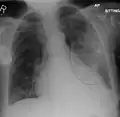

Normal AP CXR

AP CXR showing left lower lobe pneumonia associated with a small left sided pleural effusion -

AP CXR showing right lower lobe pneumonia -